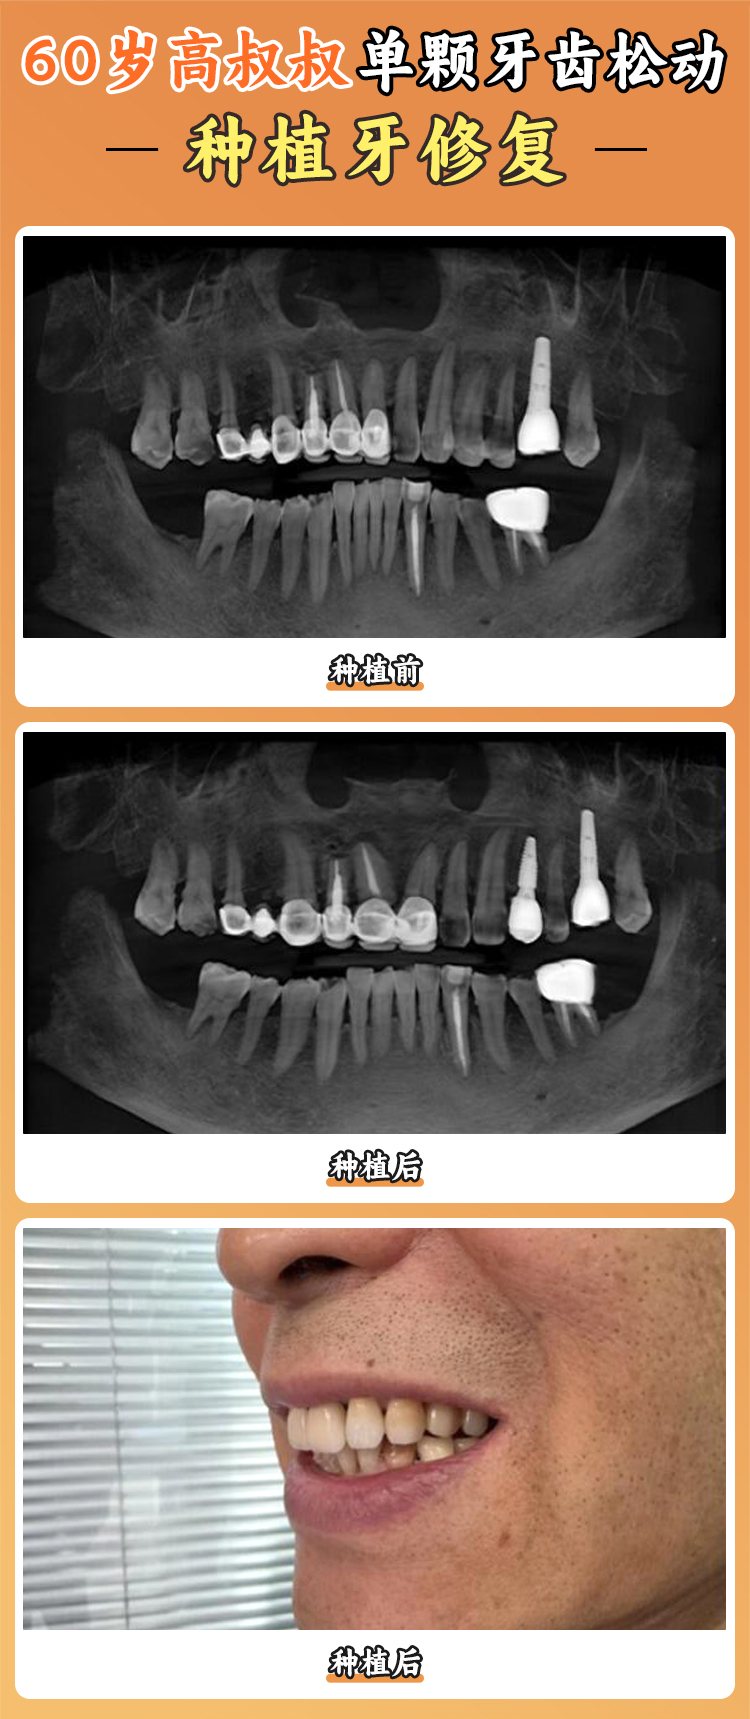

在種植牙領(lǐng)域,北京中諾口腔醫(yī)院擁有多項(xiàng)領(lǐng)跑技術(shù)。其“立得用”種植牙技術(shù)針對(duì)東方人口腔進(jìn)行了優(yōu)化,符合條件者可實(shí)現(xiàn)“當(dāng)天種牙、當(dāng)天戴冠、當(dāng)天進(jìn)食”,適配不同牙槽骨條件。該技術(shù)原理是3D導(dǎo)板定位 + 高密度種植體 + 即刻負(fù)重基臺(tái),通過(guò)德國(guó)卡瓦CT掃描,5分鐘就能生成骨骼三維模型,然后避開神經(jīng)血管,虛擬植入種植體角度,再進(jìn)行微創(chuàng)鉆孔,植入親水鈦合金種植體,末尾連接預(yù)成式牙冠并進(jìn)行咬合測(cè)試調(diào)磨。